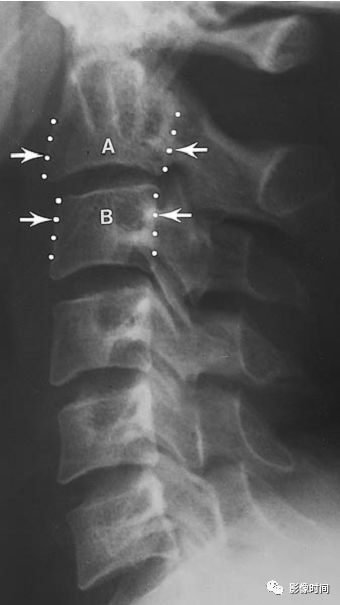

23方形椎体/方椎

方形椎体/方椎(Squared vertebral body)

侧位观,A. 椎体前缘正常轮廓是略向内凹陷的;B. 在某些疾病时,椎体前缘失去内凹的轮廓(白箭),变得平直,即称为方椎。本征象多用于描述血清阴性脊柱关节病。

典型病例

男性,33 岁。强直性脊柱炎。侧位片示胸腰段多个椎体前缘失去凹陷轮廓,呈方椎改变。